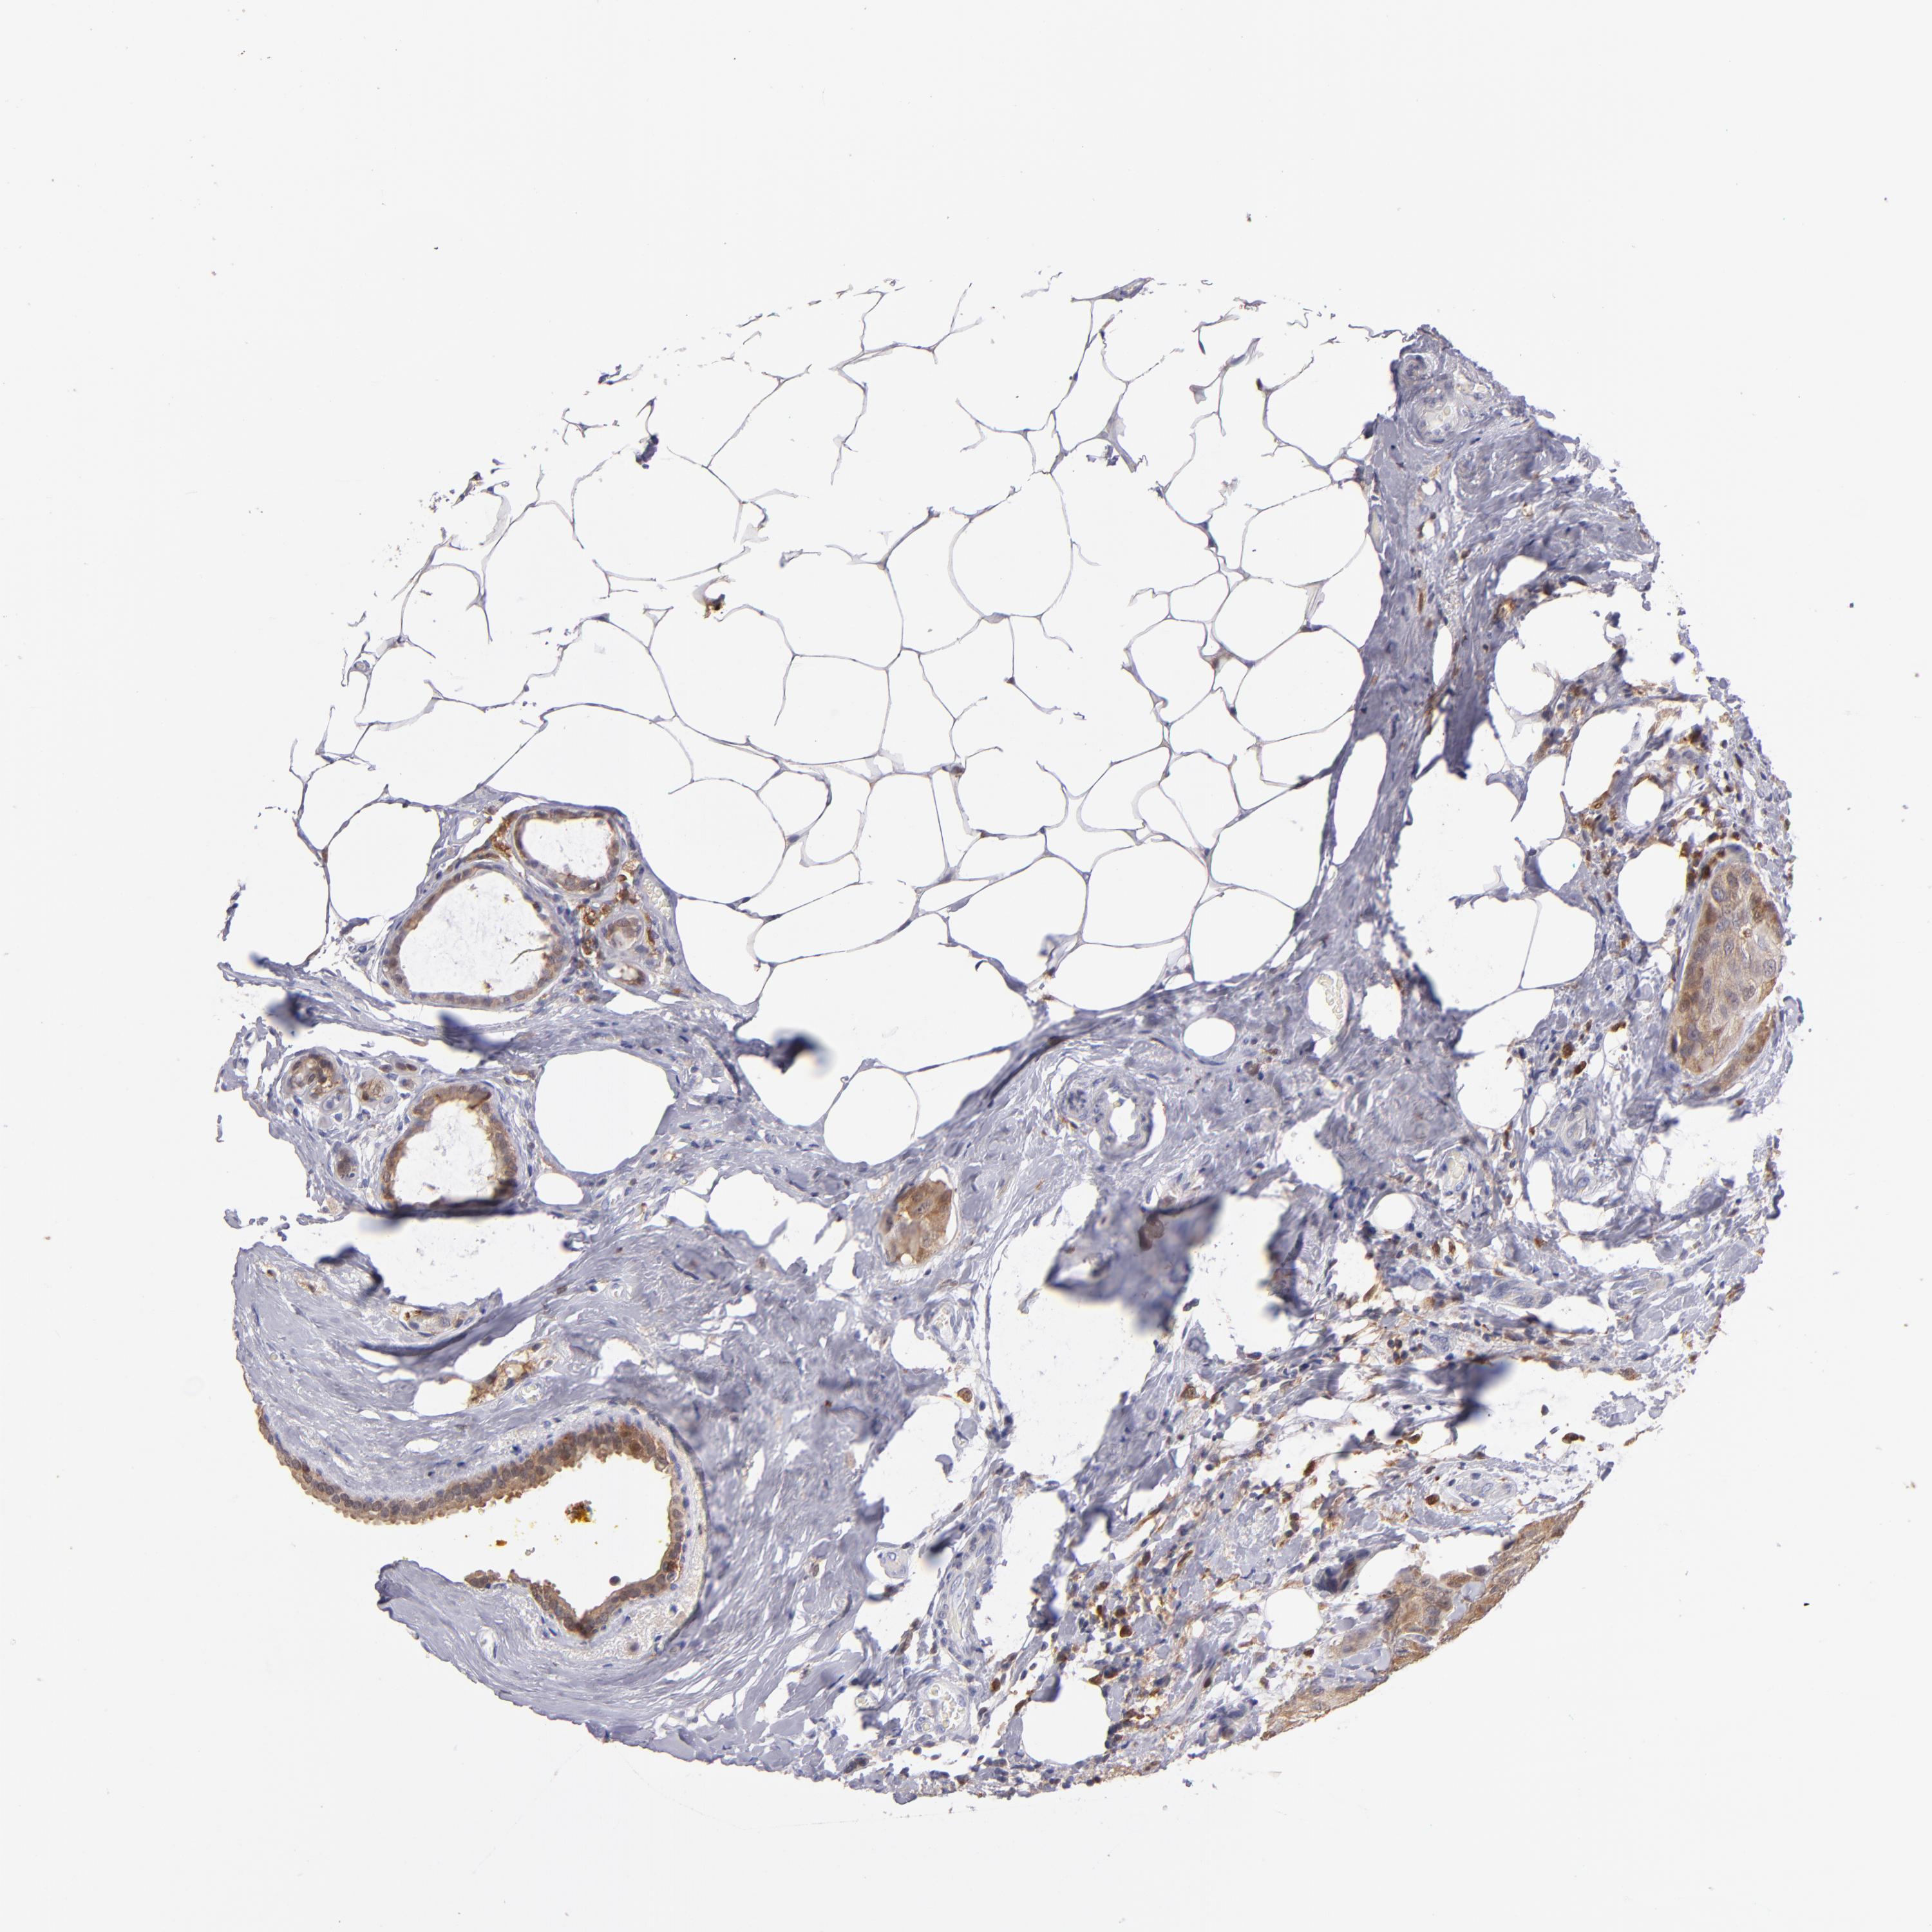

CANCER BREAST CANCER Show tissue menu

BRCA TCGA BRCA VALIDATION PROTEIN EXPRESSION

ANTIBODIES

AND

VALIDATION